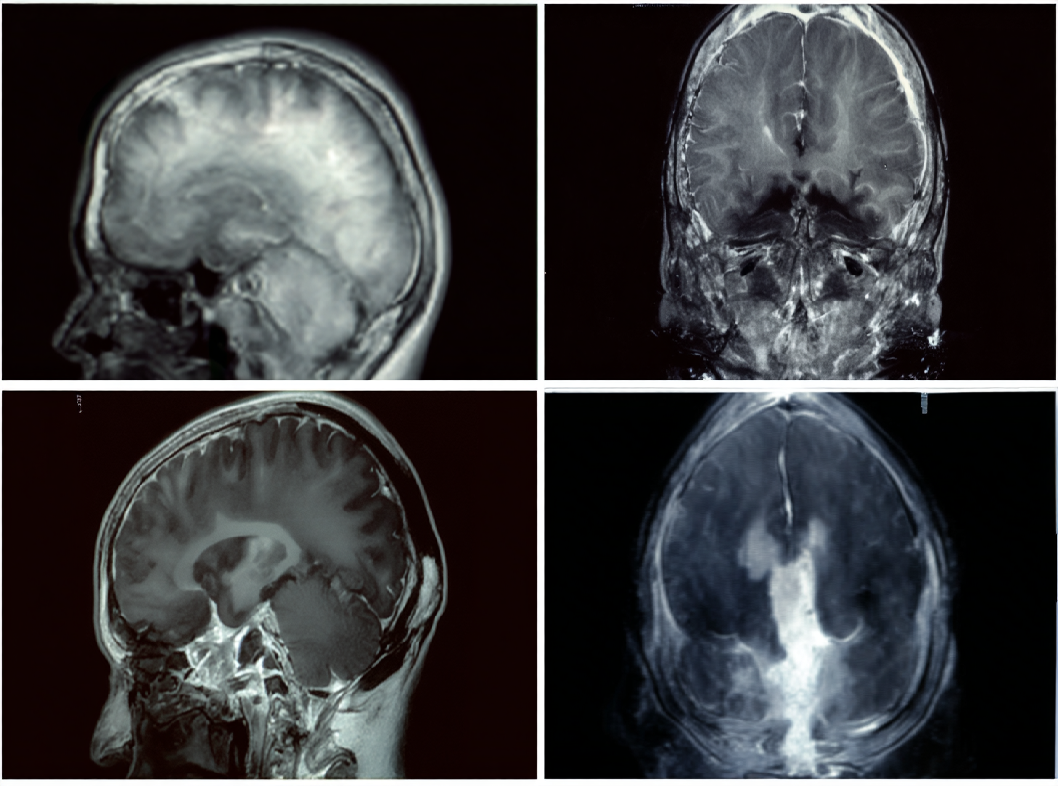

- Образовательные методы. Магнитно-резонансная томография (МРТ) или компьютерная томография (КТ) могут использоваться для визуализации гипофиза и надпочечников, а также для выявления возможных опухолей.

Диагностика болезни Иценко-Кушинга часто требует внимательного медицинского наблюдения и комплексного подхода. После диагностики врач может решить о дальнейших исследованиях и лечении, включая хирургическое вмешательство для удаления опухолей, если они присутствуют.